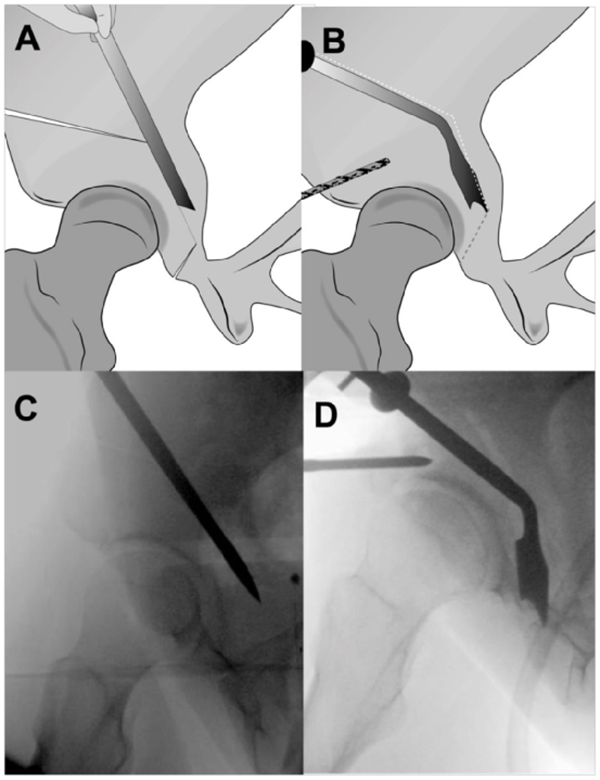

A.后柱截骨。B.成角骨刀截断残留连接处,截骨块充分游离。C.髂骨斜位透视图显示截骨线。D.游离截骨块